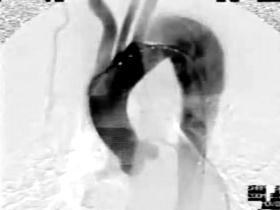

3.大動脈瘤に対するステントグラフト内挿術

大動脈ステントグラフト